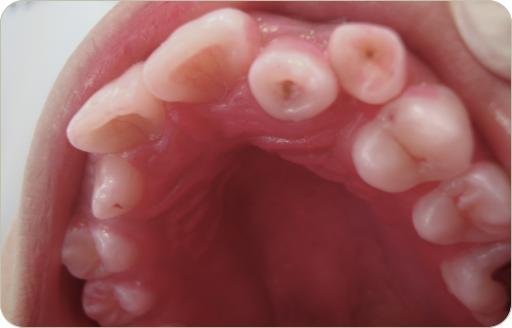

Especialistas en Medicina y Patología Bucal 2010

1